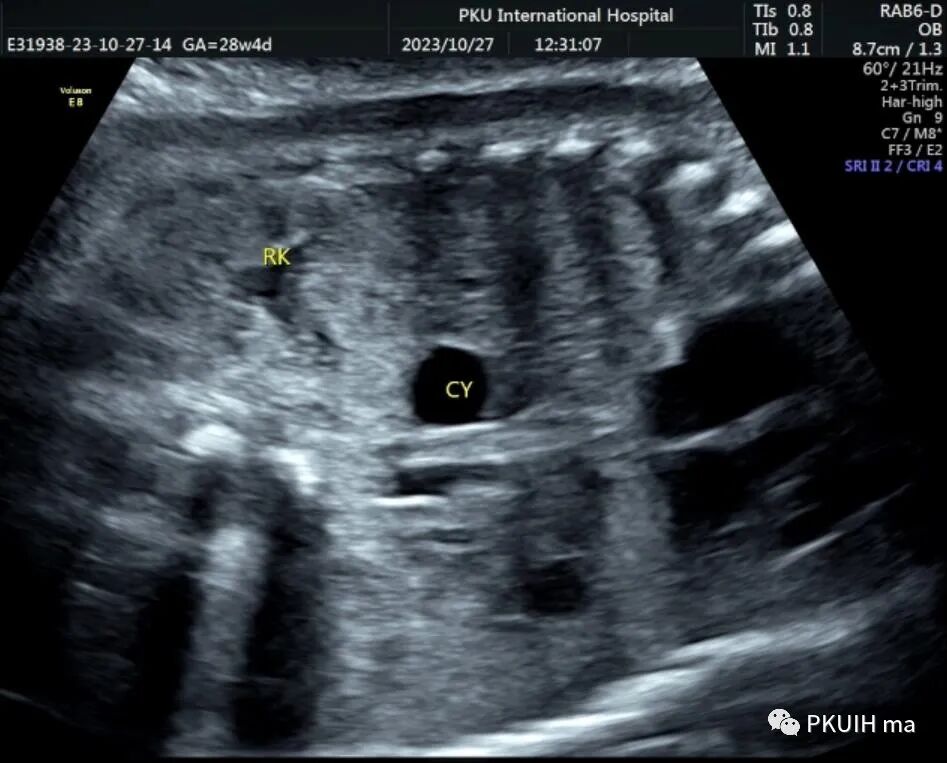

孕妇在之前超声检查中均未见异常,在28周常规超声筛查中发现右侧肾上腺区见一囊肿回声,大小约1.3x1.0cm。随访观察中发现囊肿逐渐增大,胎儿其他各项指标未见明显异常。目前仍在定期随访中